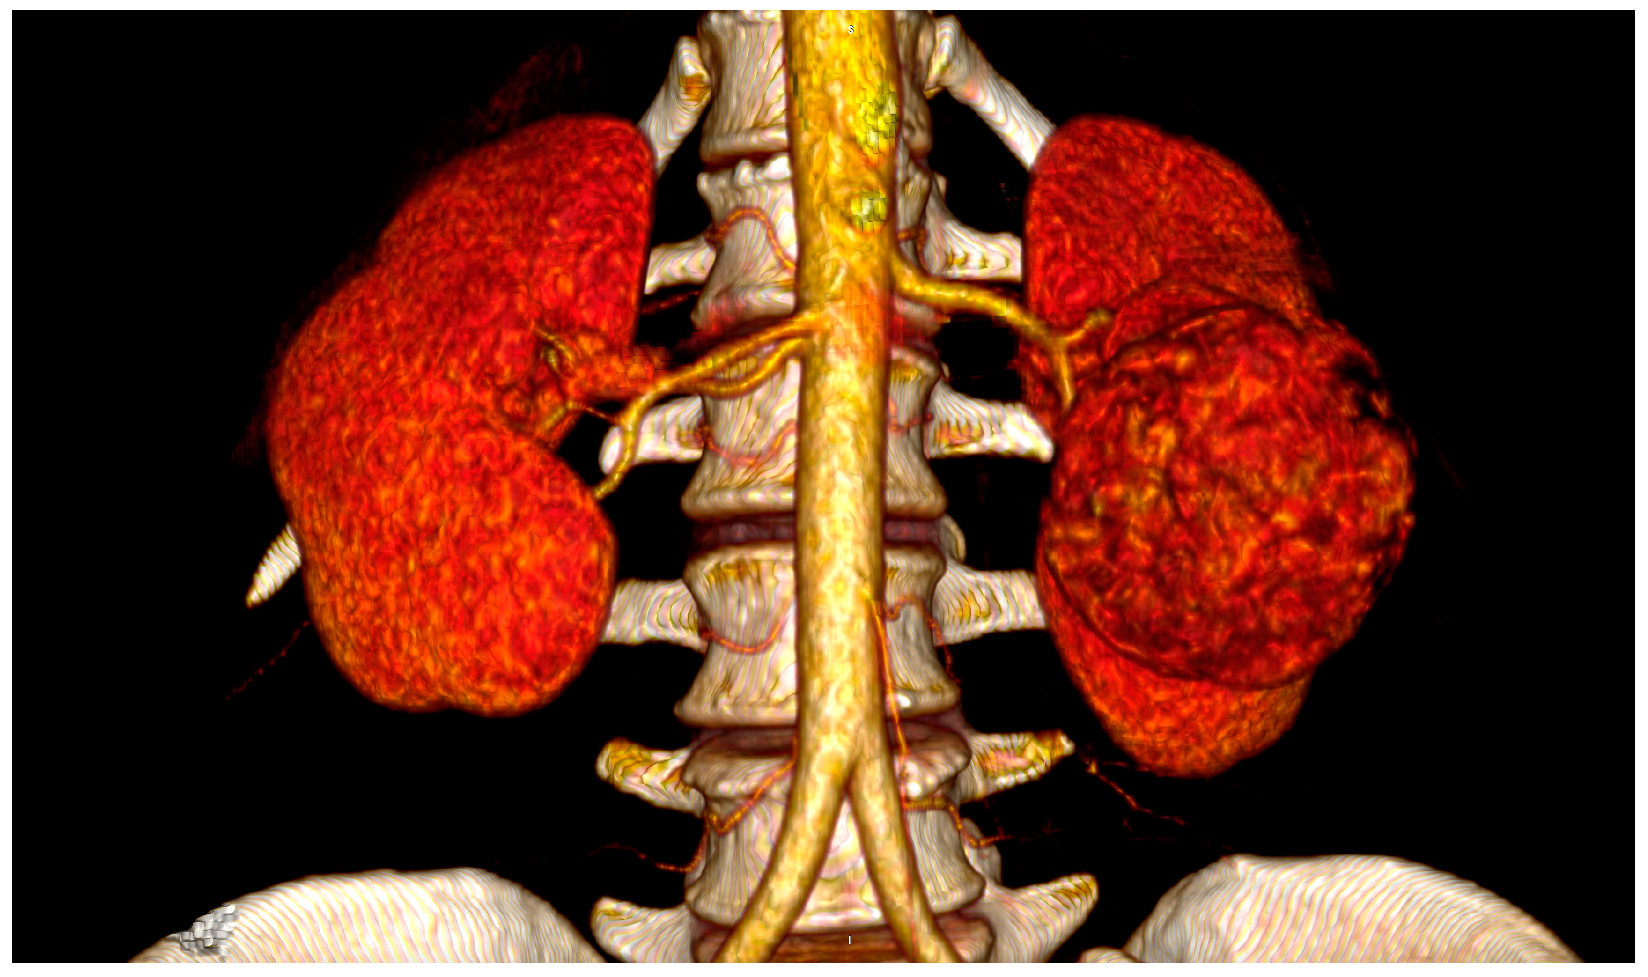

2.4. Spatial Relationships

3.2. Risk Factors

3.3. Pathogenesis, Prevention and Diagnosis